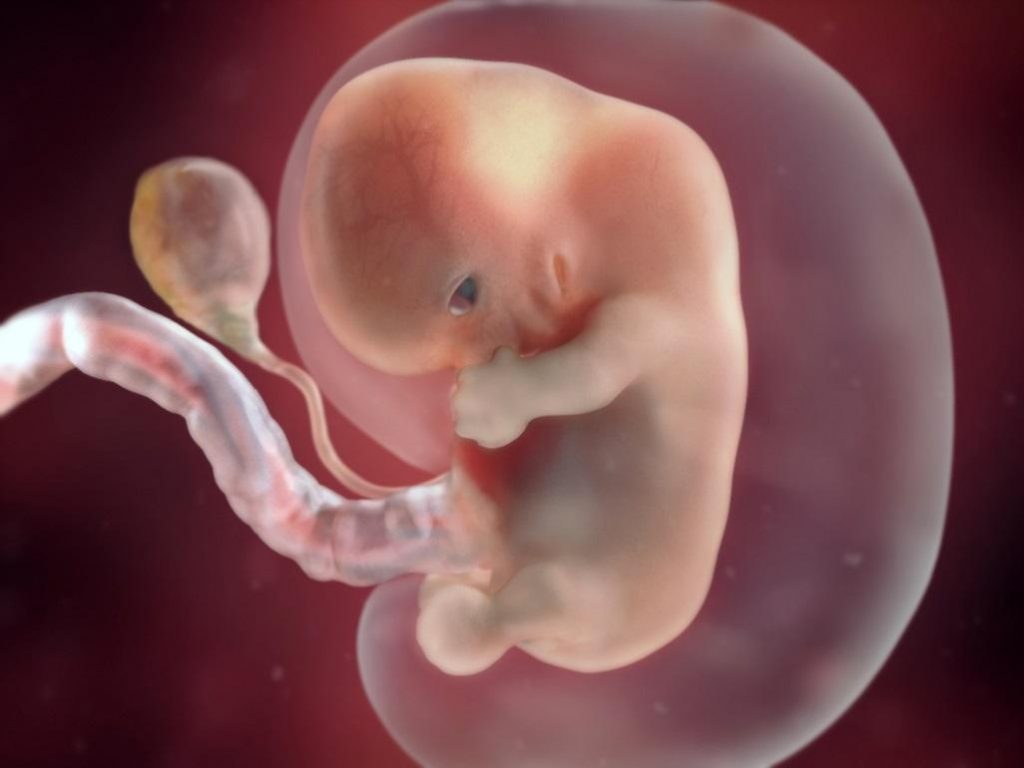

Беременность 6 Недель Развитие Фото

Беременность 6 Недель Развитие Фото 108 фотографий